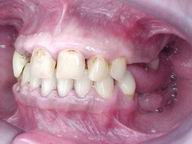

Reabilitação funcional e estética em ambas as arcadas

com próteses fixas e removíveis de encaixe de precisão.

Vista Lateral Direita

Vista Lateral Esquerda